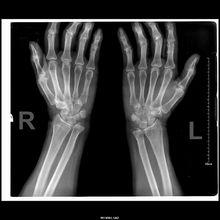

骨頭錯位● 及時檢查扭傷嚴重不妨對關節做x光照像檢查,因為嚴重扭傷與骨折經常不易區分。如確診,可在扭傷的肢體或手指部位鑄敷石膏模。

骨頭錯位骨折出現後,沒有錯位就稱為“骨裂”。如果受到外傷的暴力較大,骨折後,骨折兩端就可以完全錯開。骨折錯開以後,受傷部位的外形就可以發生變化,也就是說出現了畸形,受傷部位在活動時就可聽見在骨折的兩個斷端間可發出摩擦的響聲,而“骨裂”一般不會出現這樣的聲音,如果我們用過大的力量來搬動的話,原來的“骨裂”可能會發生錯位,所以應該絕對注意不應在外傷後對受傷部位做不必要的增加外力的檢查動作。

骨折的錯位可以因暴力的大小不同和作用方向的不同而發生多種移位,如發生成角、短縮、側方和鏇轉的移位,有的可以是單一種的移位,也可以是多種的移位。在下肢如發生短縮的移位,就可出現下肢的不等長;發生鏇轉的移位,在骨折癒合後,會發生走路時內或外八字的步態。